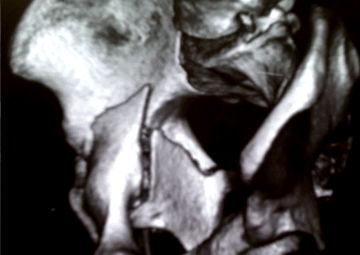

Complex Trauma Care

Specialized treatment for severe fractures and injuries to restore function and mobility.